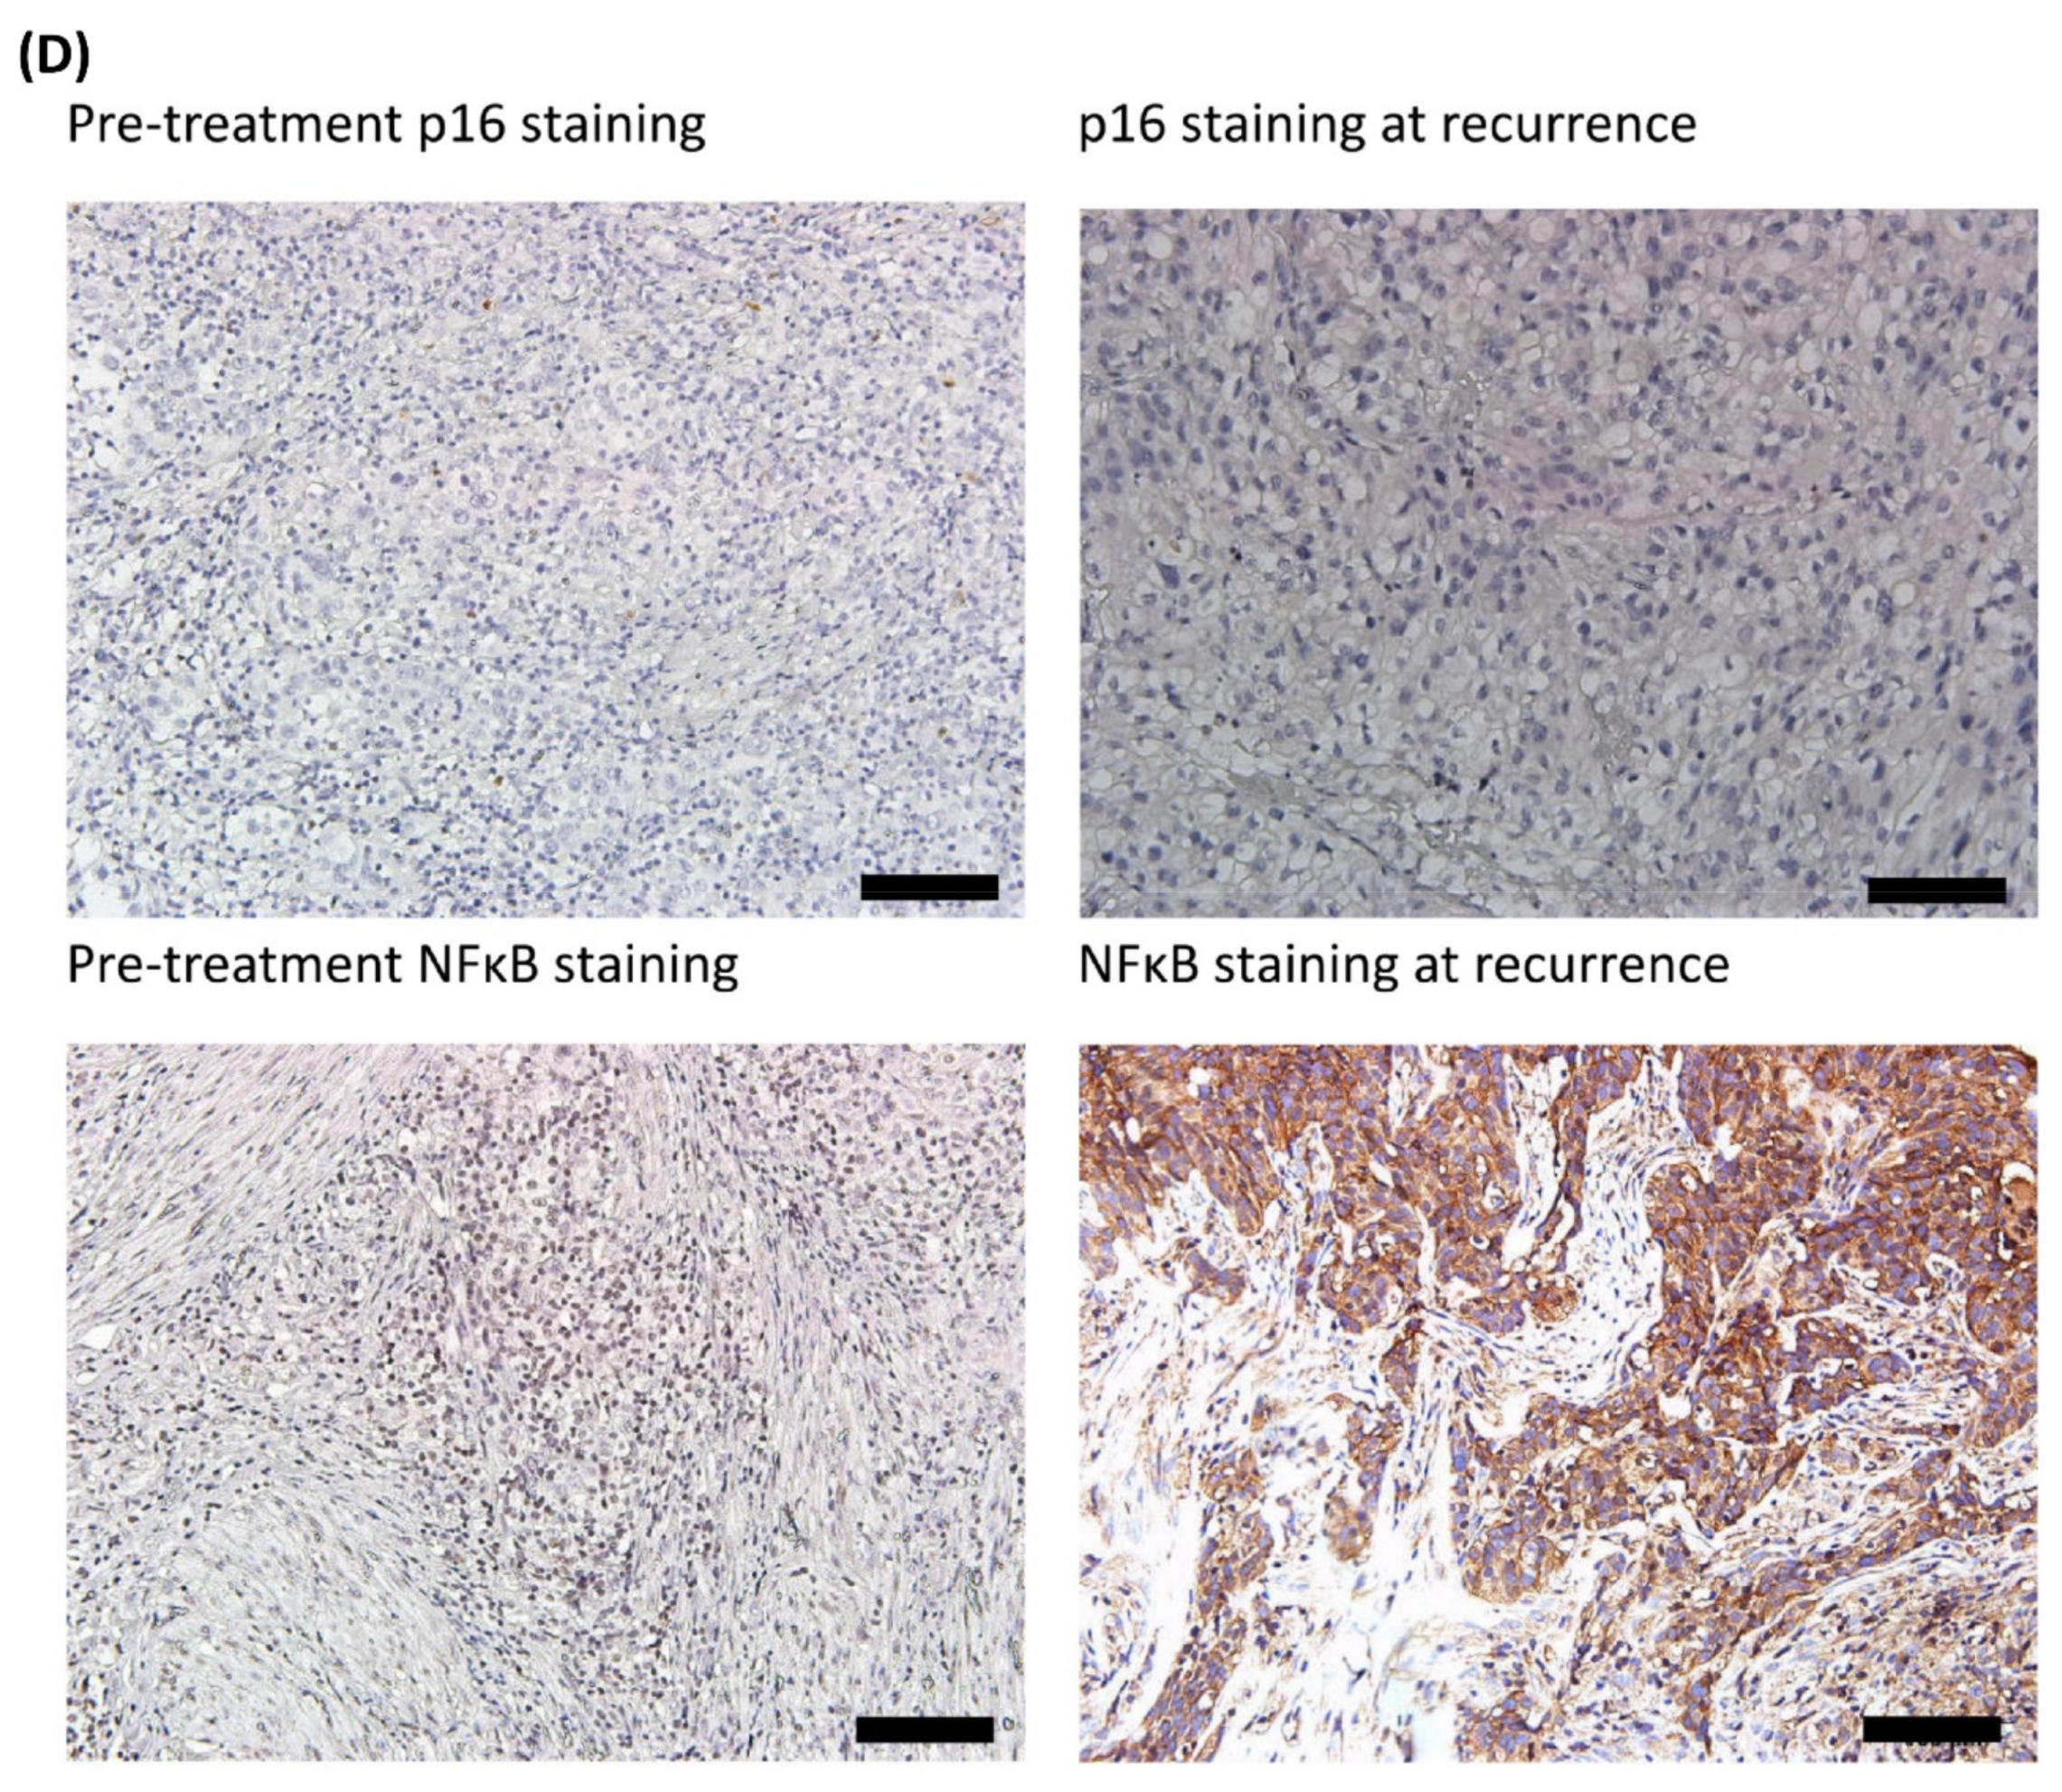

3.3. Comparisons of Immunostaining of NFκB between Pre-Treatment Samples and Recurrent Samples